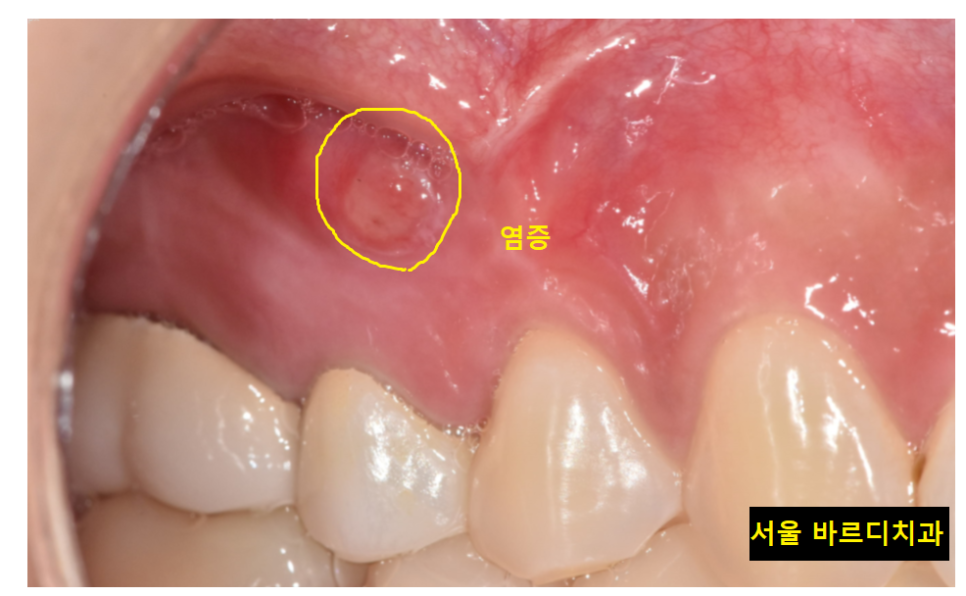

육안으로 보기에는 물집 잡힌 것처럼

잇몸이 볼록하게 부풀어 올라와 있었습니다.

염증이 잇몸 밖으로 빠져나온 것이죠.

23.10.15

기존 재료를 제거하고

mta로 재신경치료 마무리 한 모습입니다.

처음 망월동 치과 방문하셨을 때는

뿌리 끝이 검정색으로

염증이 있는 상태였는데

많이 줄어든게 보이실껍니다.

뿌리 끝 검게 잡힌 염증도

재신경치료 후

싸악 사라졌습니다!!